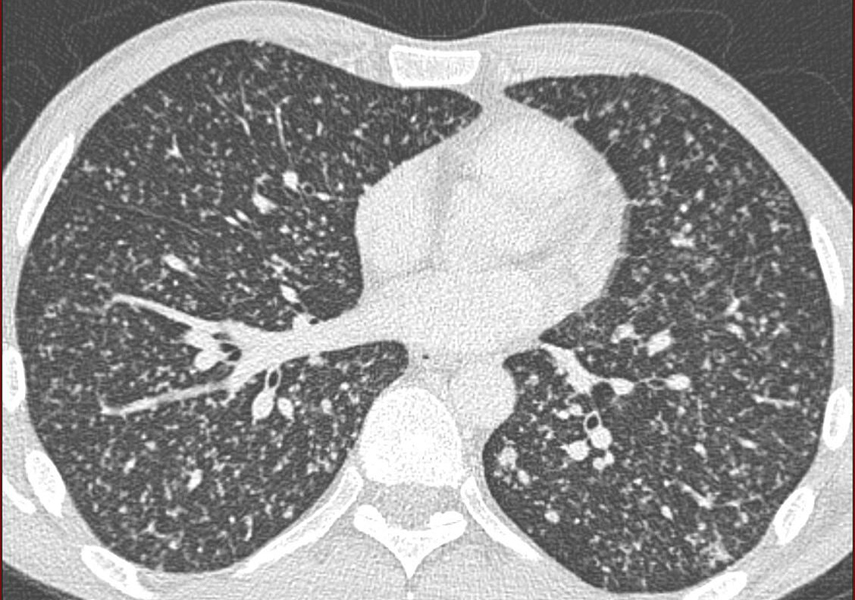

Antécédent cancer du sein en rémission. Syndrome? diagnostic?

Syndrome rétoculo-nodulaire => lymphangite carcinomateuse